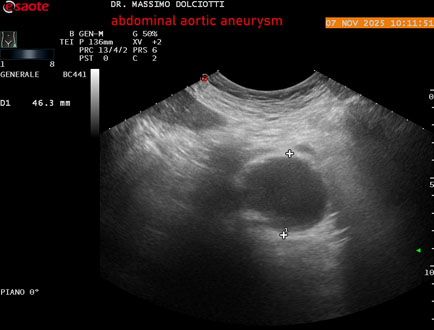

Data inserimento: 11/11/2025

Ecografia del: 07/11/2025

Strumento: Esaote MyLab Eight

Sonda: Convex Multifrequenza 1-8 MHz

Età Paziente: M 60 anni

Motivazione dell'esame: follow up per aneurisma dell'aorta addominale.

Commento all'esame: le immagini ed il video documentano la presenza dell'aneurisma dell'aorta addominale sotto-renale, con diametro antero-posteriore massimo documentato di 47 / 48 mm.

Conclusioni: aneurisma dell'aorta addominale in follow up (abdominal aortic aneurysm follow-up).

Presentazione: Dr. Massimo Dolciotti - Ancona